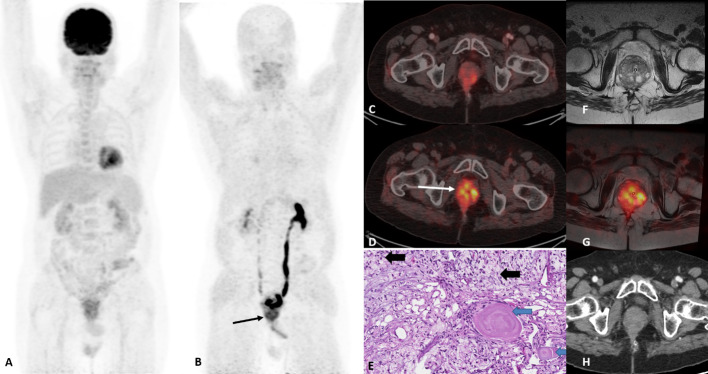

Signet cell rectal carcinoma with prostatic involvement detected by FAPI-04 PET-MRI fusion.

A 60-year-old male patient diagnosed with mucinous adenocarcinoma of lower third of rectum underwent abdominoperineal resection and permanent colostomy followed by adjuvant chemotherapy. Response evaluation with F-18 FDG PET-CT showed a complete metabolic response. After 6 months, CEA levels started increasing and clinically a recurrence was suspected. A restaging FDG PET-CT showed no obvious malignant disease. Patient presented again within a month with complaints of urinary retention and haematuria. CEA levels were further elevated, and Ga-68 FAPI-04 (FAPI) PET-CT was performed. FAPI PET-CT revealed prostatic and seminal vesicle disease involvement. Additionally, an MRI of pelvis was done and fused with FAPI PET for confirmation of prostatic involvement.